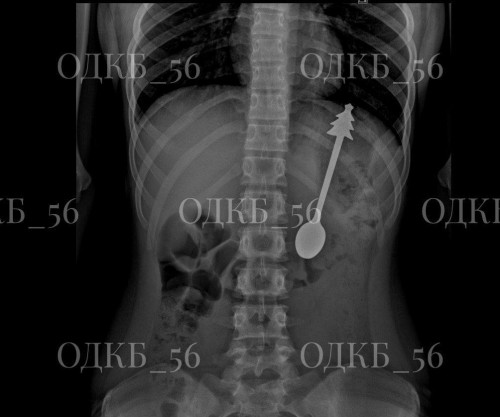

Ребенок поглотил ложку длиной 14 см: оренбургские врачи без разрезов спасли ребенка

07.02.2026В областную детскую больницу поступил мальчик, случайно проглотивший металлическую ложку.

Диагностика с помощью рентгена показала, что в желудке ребенка находится ложка длиной 14 сантиметров.